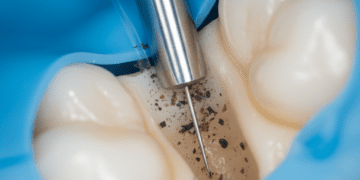

Esmalte: É a camada mais externa que cobre a coroa dentária, formada predominantemente por minerais, especialmente hidroxiapatita, que confere alta resistência e proteção contra o desgaste e agentes externos. Por ser avascular, o esmalte não possui células vivas e não se regenera após danos.

Dentina: Localizada logo abaixo do esmalte e do cemento, a dentina é uma camada menos mineralizada e mais porosa, composta por túbulos dentinários que permitem a condução de estímulos ao interior do dente. É responsável por fornecer suporte estrutural ao esmalte e transmitir sensações dolorosas ou térmicas.